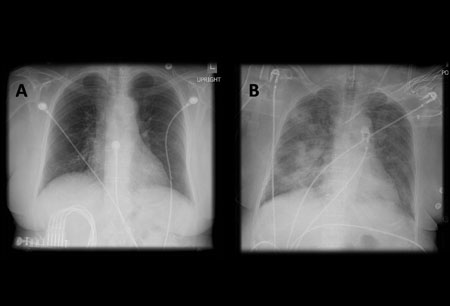

Uma radiografia torácica deve ser obtida no início da avaliação da tosse crônica.[38] Embora não seja diagnóstica das causas mais comuns, os achados podem facilmente desviar a avaliação para causas de maior gravidade como doenças pulmonares estruturais. Eles incluem câncer pulmonar, fibrose pulmonar, tuberculose, bronquiectasia, pneumonia, aspiração e sarcoidose.[Figure caption and citation for the preceding image starts]: Radiografia torácica mostrando hiperinsuflação em paciente com DPOC. A hiperinsuflação é causada pelo componente de enfisema na DPOC, em vez da bronquite crônica subjacente aos sintomas da tosseDo acervo pessoal do Dr. M. A. Sharifabadand, SUNY na Stony Brook School of Medicine, Departamento de Medicina Pulmonar e Intensiva, Mineola, Nova York, e Dr. J. P. Parsons, The Ohio State University Medical Center, Columbus; usado com permissão [Citation ends].

[Figure caption and citation for the preceding image starts]: A. Radiografia torácica portátil ortostática antes da aspiração; B. Radiografia torácica 1 hora após a aspiração, mostrando infiltrados alveolares difusos bilaterais, piores nas bases do lado direitoDo acervo pessoal do Dr. S. Murgu e do Dr. H. Colt, Universidade da Califórnia / Irvine Medical Center [Citation ends].